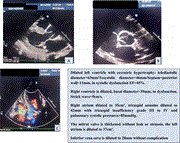

Management of calcified right atrial myxoma extending into the inferior vena cava: a case report

Mohammad Qaiser Aziz Khan and others

Journal of Surgical Case Reports, Volume 2023, Issue 10, October 2023, rjad568, https://doi.org/10.1093/jscr/rjad568